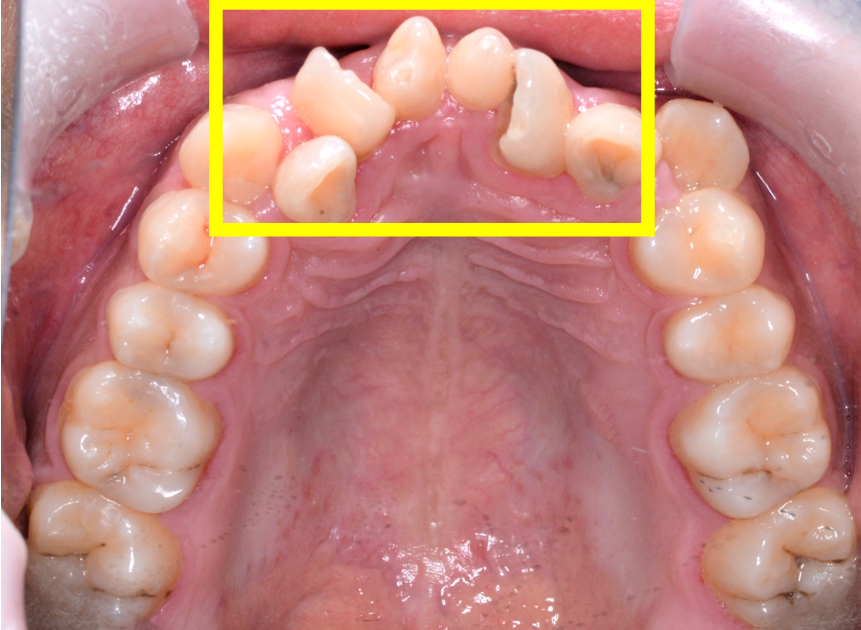

牙齿敏感,口腔中不可忽视的小问题这种疼痛通常来得迅速,且疼痛感强烈,但持续时间较短。牙齿敏感的原因有哪些?1. 龋齿原因:龋齿突破牙釉质发展到牙本质时,会引起酸软感。越接近牙髓,敏感程度越高,牙齿敏感症状会更加显著。解决办法:如果只是单纯的小洞,不需要太过惊慌,请医生充填修补即可。但如果蛀牙很深,那...

牙齿爱敏感,总是遇冷热都酸痛,是哪里出了问题?听医生详细讲解会侵蚀牙釉质或刺激牙齿神经,增加敏感风险。 5. 牙齿美白或修复治疗后遗症某些牙齿美白产品或修复治疗(如牙齿漂白、牙冠安装)可能暂时使牙齿更加敏感。此类敏感通常是短期的,但如果持续,应咨询专业医生。 三、如何预防牙齿敏感?牙齿敏感虽然常见,但通过良好的口腔护理和生活...

补牙后牙齿变得敏感,正常吗?看完这篇文章你就懂导致敏感。 而且,当龋齿较深,患处距离牙神经较近时,补牙手术可能会对牙神经产生刺激,引起牙神经炎症,从而导致牙齿敏感。术后牙齿敏感还可能是填充物过高或过低导致的,这种情况会导致咬合不齐,进而出现牙齿敏感、疼痛等症状。 补牙后牙齿敏感怎么办? 补牙后,短期内有牙齿敏感...